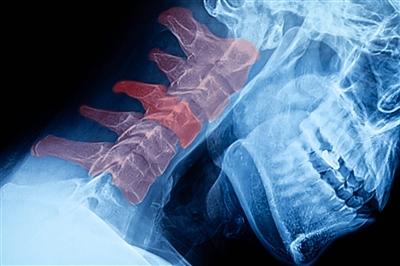

“With every inch that our head moves forward and down, our neck has more weight to bear. In a neutral position, the human head weighs about 10 pounds. You can double that and triple that weight with every inch that you move it forward, which ultimately puts an incredible amount of strain on your neck and spine,” explains Dr. Murray.

The most common symptom of tech neck is, of course, neck pain and discomfort, but you might notice other aches and pains too. Headaches, shoulder pain, neck spasms and weakness or tingling in your arms as a result of a pinched nerve can also be a result of tech neck. Long term, your positioning can also cause a herniated disc or affect the curvature of your spine.